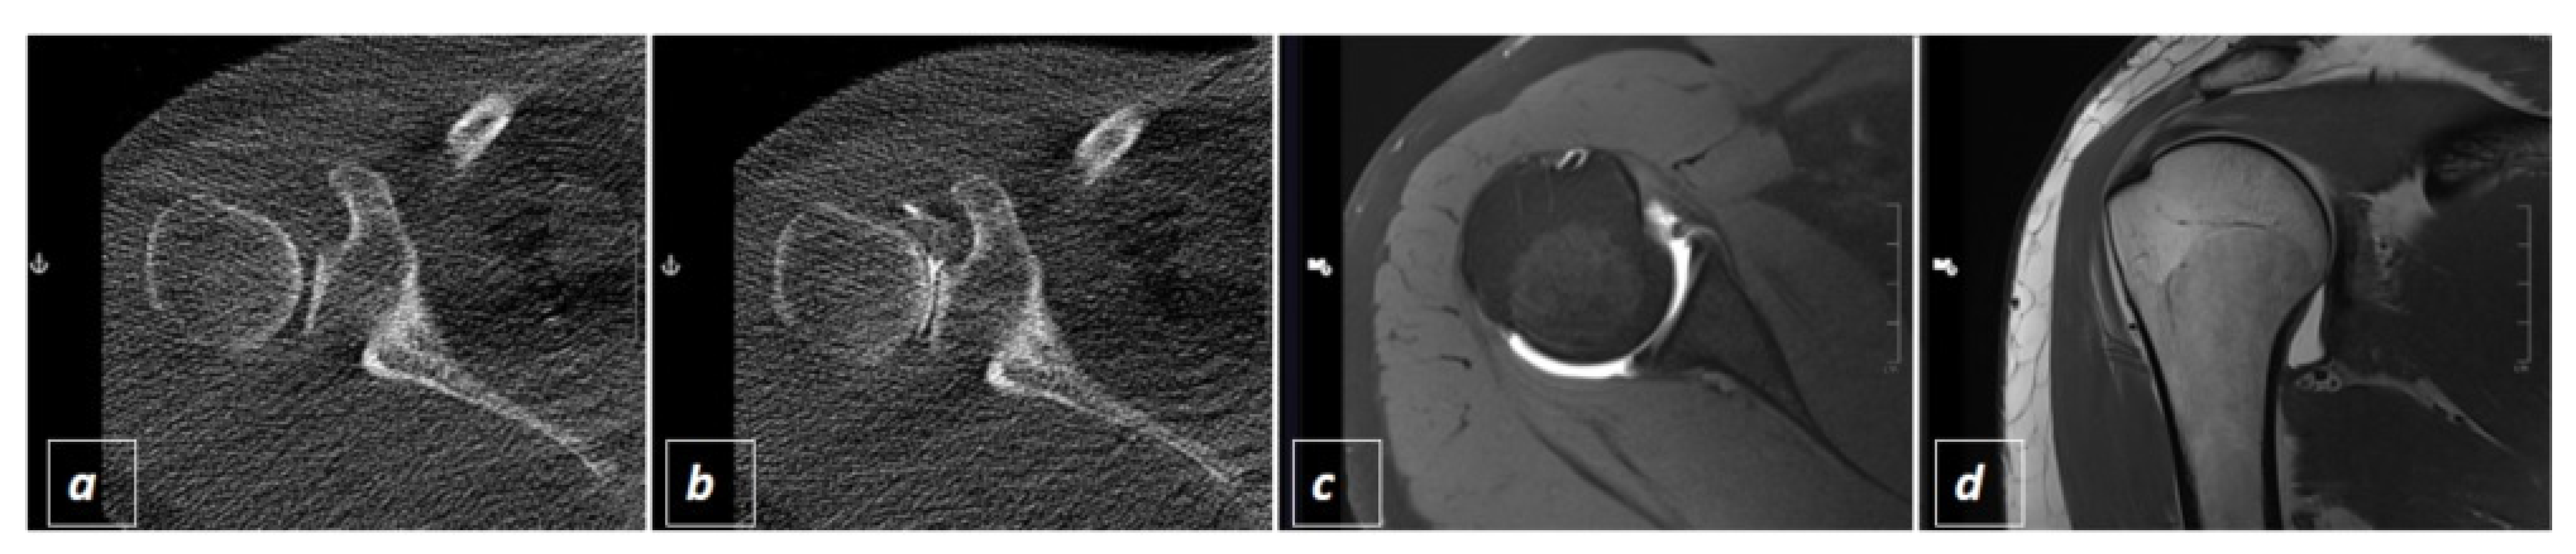

2.2. CT-Guided Joint Injections

2.3. The Three Different Examination Protocols

2.4. Radiation Exposure and Interventional Success